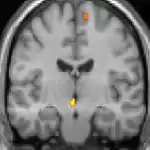

|  |  |  |

| La tomographie par émission de positons (TEP) montre les zones du cerveau étant activées durant la douleur | ||

| La morphométrie voxel par voxel (VBM) montre les différences structurelles des zones du cerveau | ||

Les images par tomographie à émission de positron indiquent les régions du cerveau qui sont activées lors de la douleur, par rapport aux périodes sans douleur. Elles montrent les régions du cerveau qui sont toujours actives durant la douleur en jaune/orange (appelé "matrice-douleur"). La zone au centre (dans les trois vues) est spécifiquement activée uniquement pendant la crise. Les photos sur la ligne du bas (effectuées par VBM) montrent les différences structurelles entre les patients souffrant d'AVF et des personnes saines : seulement une partie de l'hypothalamus est différente[50],[51].